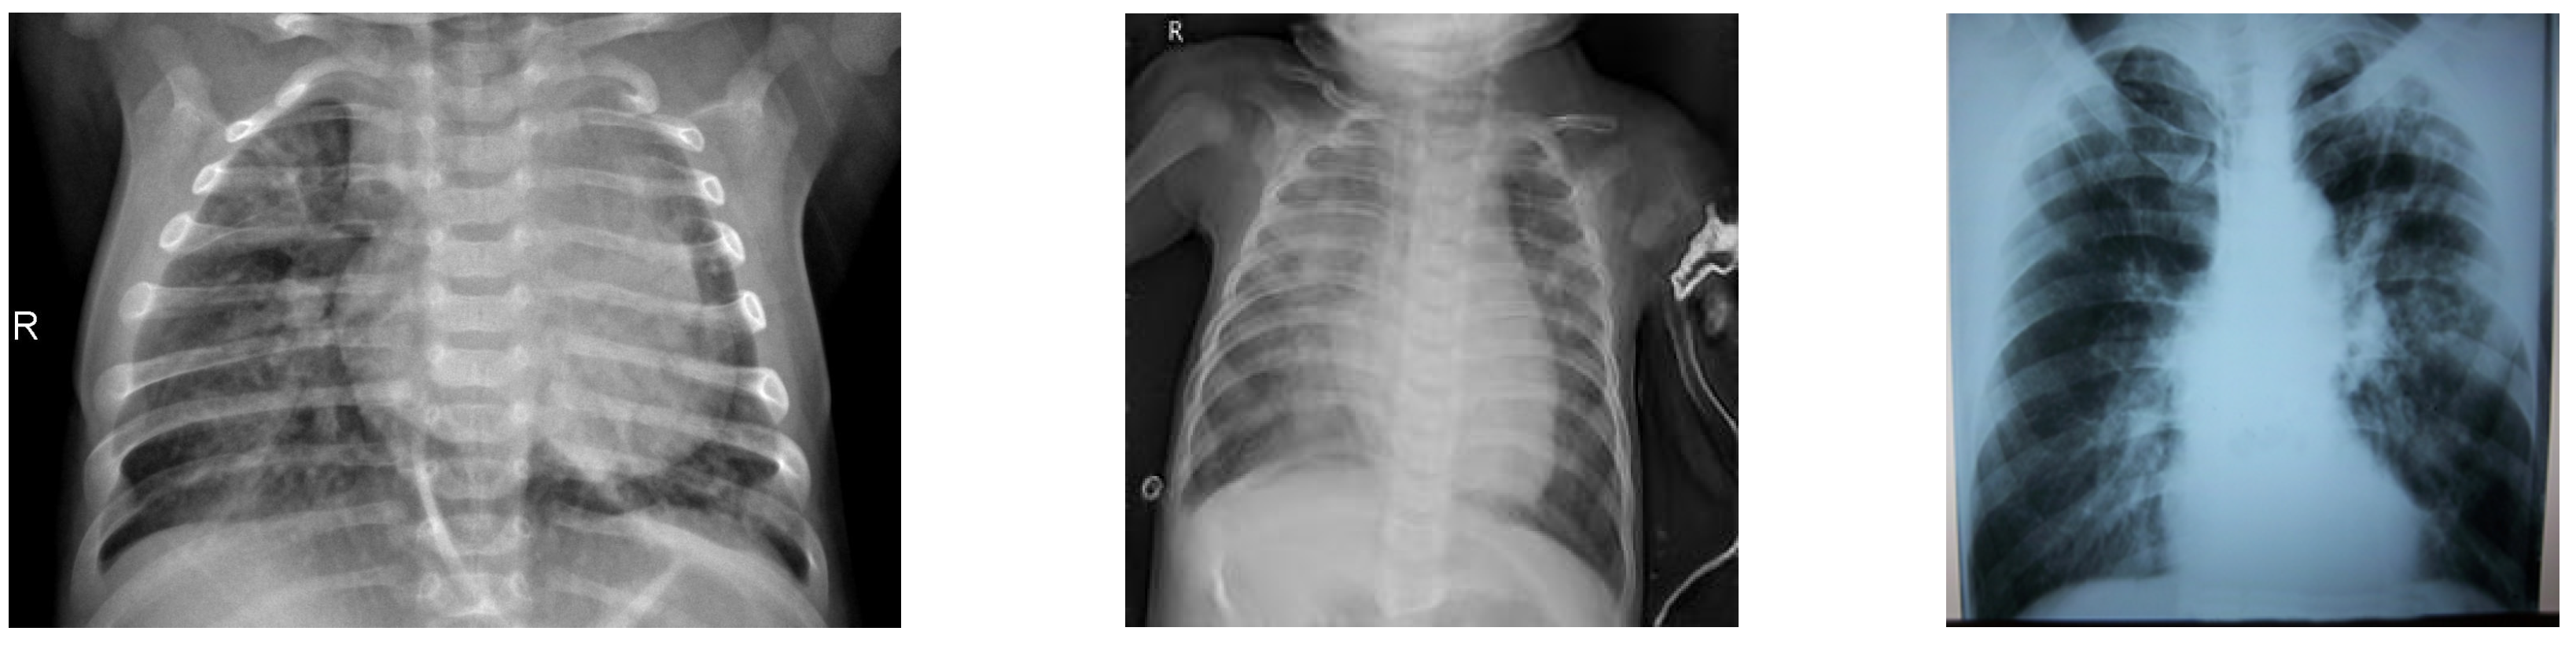

3.1. Dataset

4.1. Generating the DCGAN Image